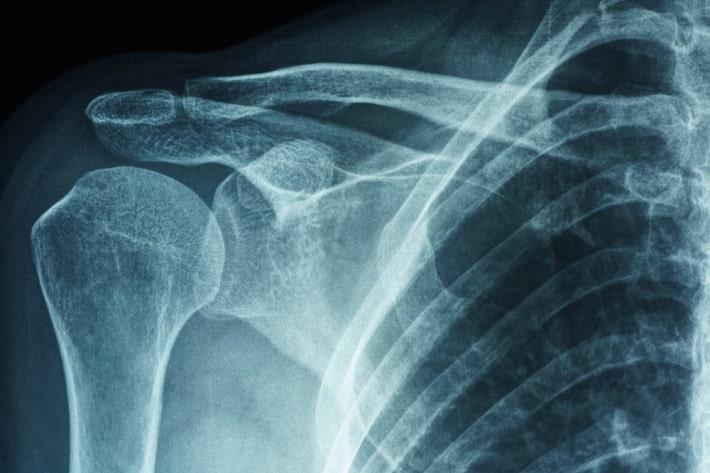

צילום: PK289 | Shutterstock

צילומי רנטגן - מבנים צפופים, כגון עצם, מופיעים בבירור בצילומי רנטגן. צילומי רנטגן יכולים להציג בעיות אחרות בכתף כגון דלקת פרקים.